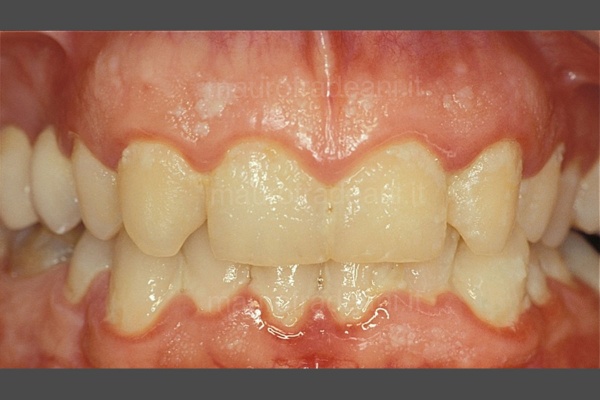

L’impiego di tecniche di previsualizzazione del risultato finale quali il mock-up, oltre a facilitare al paziente la comprensione del piano di terapie proposto, gli permette addirittura di testare per qualche ora o per qualche giorno il nuovo sorriso. Preparazioni dentali minimali permettono la massima preservazione di struttura dentale e, in gran parte dei casi, evitano il ricorso alla somministrazione di anestesia.

Le corone dentali in ceramica si possono realizzare sia su denti naturali sia su impianti osteointegrati, qualora la compromissione irrimediabile del dente ne abbia resa necessaria l’estrazione.

Richiedono una preparazione dentale talmente minimale da non dover ricorrere, nella maggioranza dei casi trattati, alla somministrazione dell’anestesia.